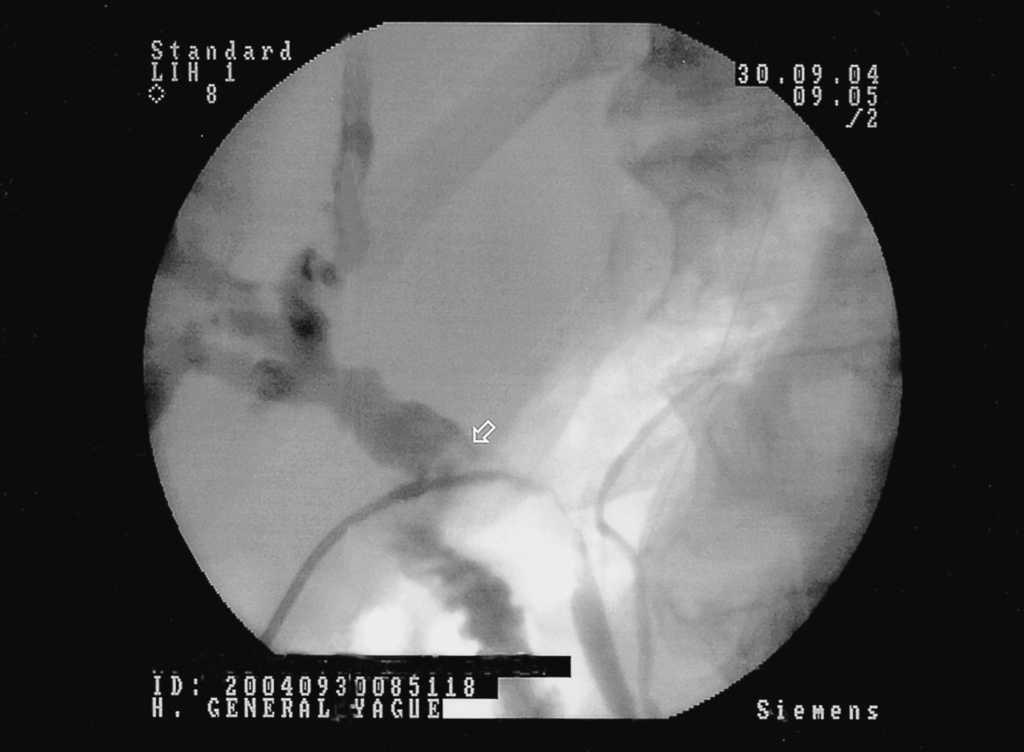

Se realiza una colangiorresonancia magnética (fig. 1), donde se observa una dilatación de la vía biliar intrahepática y del colédoco con stop brusco en su porción media. Se decide valorar la posibilidad de colangiocarcinoma o tumor de cabeza de páncreas que no se ve en este estudio.

Fig. 1. Colangiorresonancia magnética, que demuestra una dilatación de la vía biliar intrahepática y de colédoco con stop brusco en su porción media (flecha).